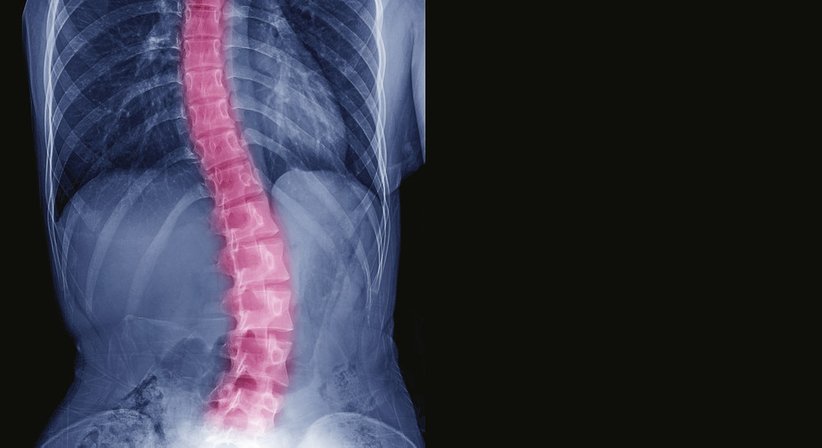

Bei einer Skoliose handelt es sich um eine Fehlstellung der Wirbelsäule/Wirbelsäulenverkrümmung - es liegt eine Verdrehung der einzelnen Wirbelkörper um ihre Längsachse und gleichzeitig eine seitliche Verkrümmung der Wirbelsäule vor. Die Wirbelsäulenverkrümmung ist dauerhaft. Eine Skoliose kann verschiedene Ursachen haben, in einem großen Teil der Fälle bleibt die Ursache unbekannt (idiopathische Skoliose). Sie tritt typischerweise im Wachstumsalter auf.

Im Rahmen der umfassenden Abklärung werden u. a. Röntgenaufnahmen gemacht, um den Schweregrad der Skoliose bestimmen zu können. Die Therapie wird immer individuell festgelegt und angepasst und richtet sich nach dem Schweregrad der Skoliose, deren möglicher Ursache, dem Alter des Patienten und anderen individuellen Faktoren. Die Therapie zielt u. a. darauf ab eine weitere Verdrehung der Wirbelsäule und eine Verschlechterung des sogenannten COBB-Winkels (dient der Messung der Wirbelsäulenverkrümmung, Krümmungswinkel) aufzuhalten.